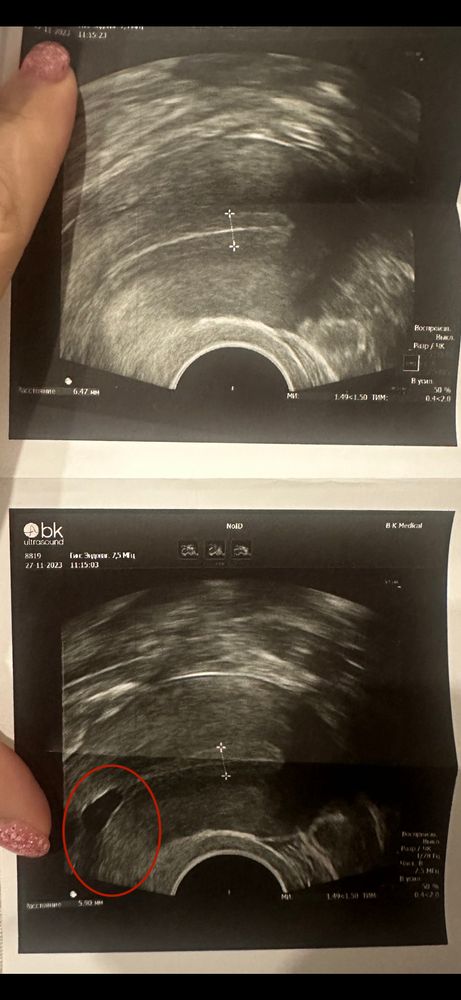

Подскажите по УЗИ

Эндометрий и все о нем (лечение, наращивание, улучшение)Добрый вечер.

что за пятно может быть?Я раньше не замечала.Врач сказала не страшно,но я так не поняла,что это,может сделать 3д узи?На что это вообще похоже?У меня 8го подсадка,я переживаю.